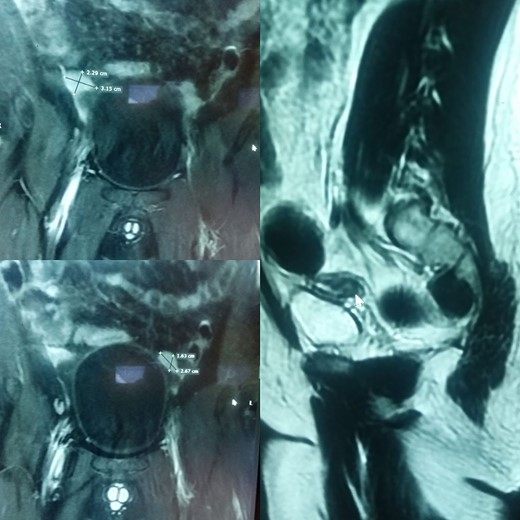

The patient and his family were counseled about the patient’s situation and were informed of the available options. A well-informed consent was obtained from him and his parents for the removal of the rudimentary uterus and both his testes. We used a laparoscopic approach to visualize the presence of testes in the right and left iliac fossas, which were attached to a rudimentary uterus, located posterior to the urinary bladder through the infundibulopelvic ligament (Fig. 2). A round ligament was also seen attaching the uterus to the abdominal wall (Fig. 3). Using the same approach, the infundibulopelvic ligament was ligated followed by the dissection of the round ligament. Uterine vessels were skeletonized and ligated. After adhesiolysis, both the testes and uterus were dissected and placed in an endobag that was then retrieved through the umbilical port and sent for histopathology (Fig. 4).

A rope-like band of connective tissue called the round ligament can be seen attaching the uterus to the abdominal wall.